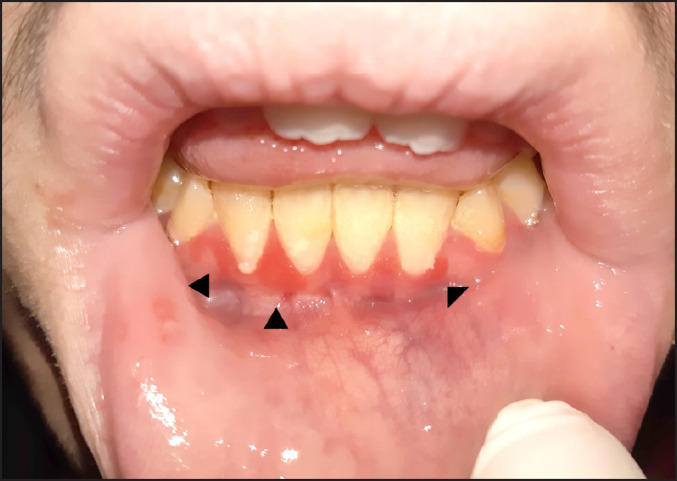

Methods: A 14-year-old boy with Asperger syndrome was referred for diagnosis and management of bright red granular overgrowths of the marginal gingiva and interdental papilla of the mandibular right incisors and marginal gingiva of the mandibular left incisor. A biopsy was performed on the interdental papilla between the mandibular right incisors.